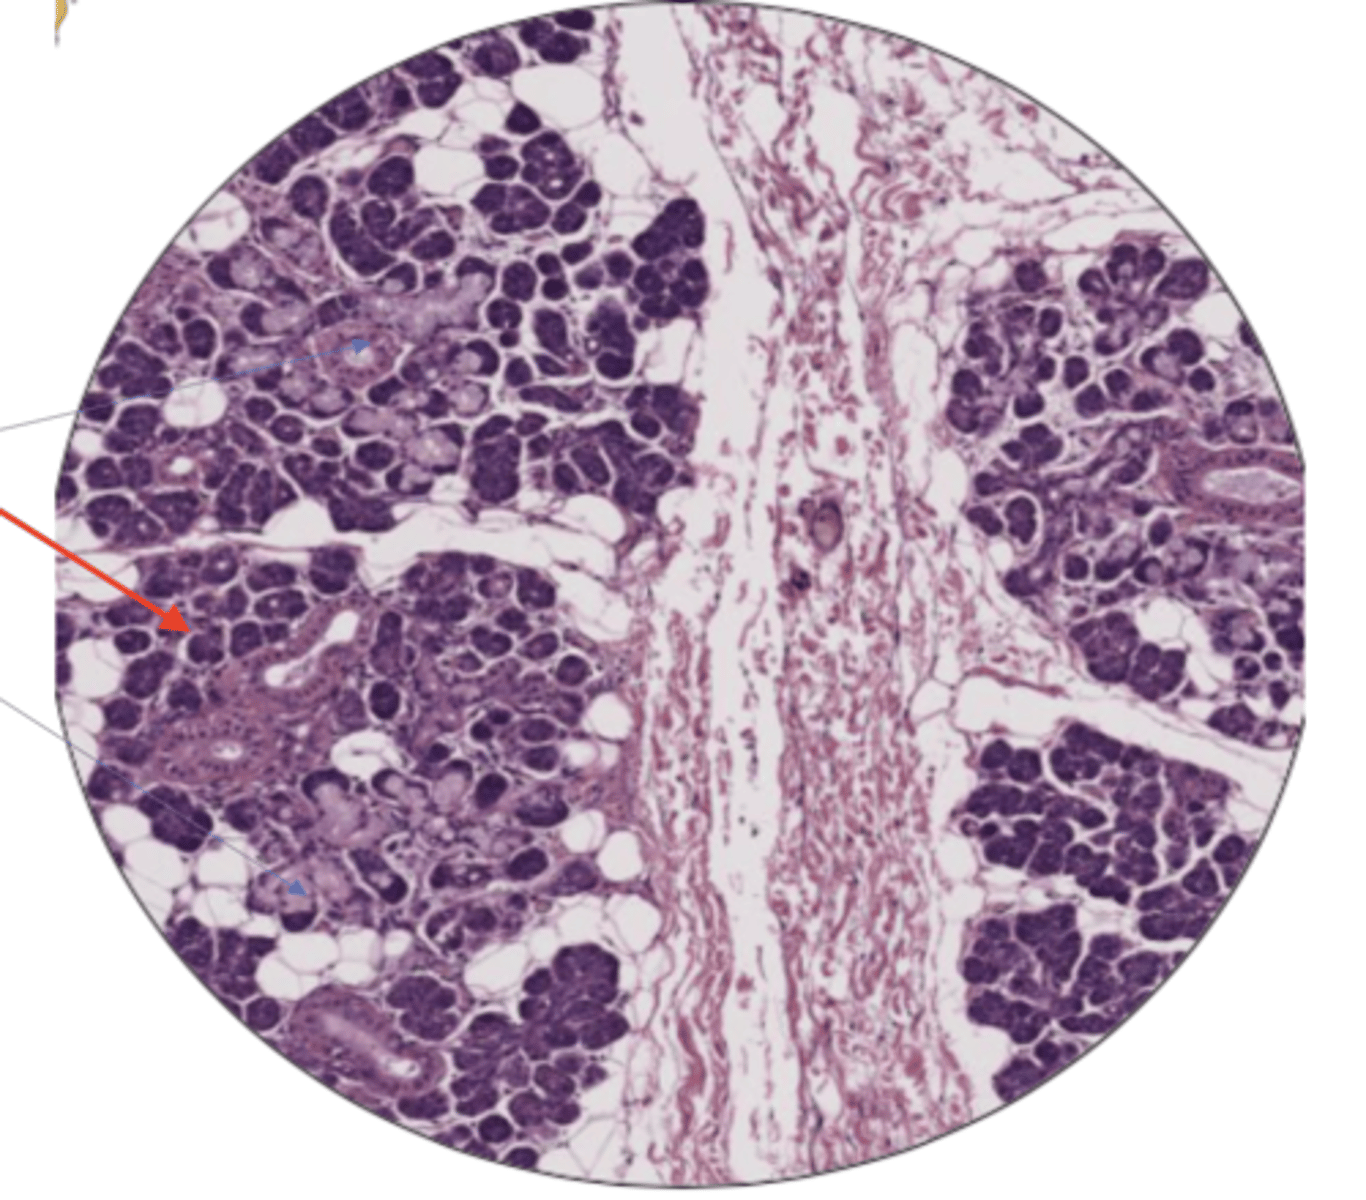

seminiferous tubule

leydig cells

sperm cell

sperm mass